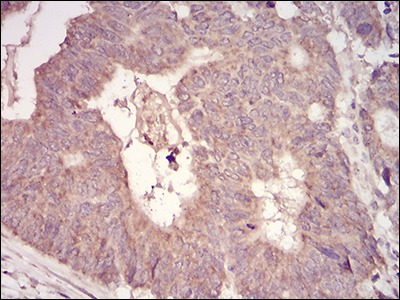

| Verified Activity | 1. Immunohistochemical analysis of paraffin-embedded human rectum cancer tissues using anti-MuRF1 antibody. Counter stained with hematoxylin. 2. Immunohistochemical analysis of paraffin-embedded huamn muscle tissues using anti-MuRF1 antibody. Counter stained with hematoxylin. 3. ICC staining MuRF1(green) and Actin filaments (red) in Hela cells. The nuclear counter stain is DAPI (blue). Cells were fixed in paraformaldehyde, permeabilised with 0.25% Triton X100/PBS. 4. Flow cytometric analysis of Hela cells with MuRF1 antibody at 1/100 dilution (green) compared with an unlabelled control (cells without incubation with primary antibody; red). ![]() ![]() ![]() ![]() |